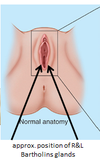

Where are the bartholins glands?

Bartholin’s glands

what is the area anterior to the pubic bone?

mons pubis

Label dans la vaginous